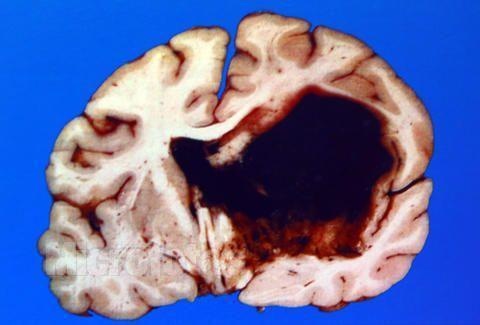

1、脑出血

这是高血压病最严重的并发症之一,男性发病率比女性高,多见于50~60岁的老年人,但年轻的高血压病人也不能忽视。高血压引起的动脉硬化,造成血管脆化,血管脆化极易造成血管破裂,从而引发脑出血。目前中国有将近800万脑中风后遗症残疾人群。